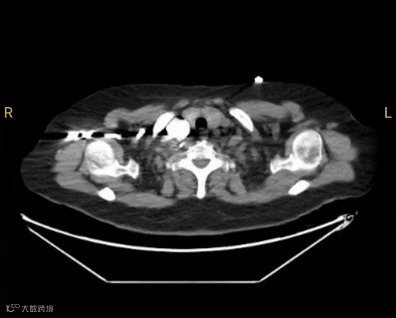

术前CT

为迅速清除血栓以降低其高危恶化风险,经综合评估后,郭振平主任团队决定为患者实施肺动脉机械取栓术。